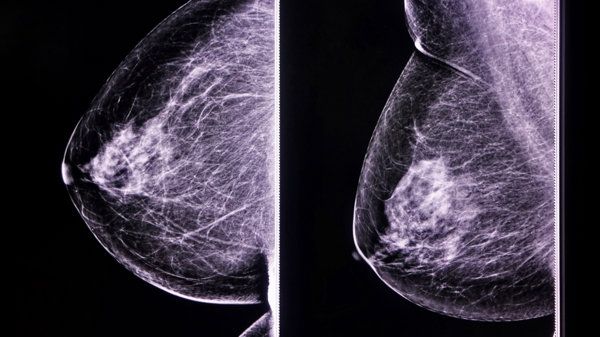

乳房主要由脂肪、结缔组织及乳腺构成。

乳房的主要组成部分包括脂肪、结缔组织及乳腺。其中脂肪占较大比例,尤其是在青春期前或绝经后,由于激素水平的变化导致脂肪重新分布;此外,在哺乳期中,乳腺也会产生乳汁储存于导管系统中。但并非所有情况下都与脂肪有关,例如某些疾病状态可能导致局部水肿或积液。